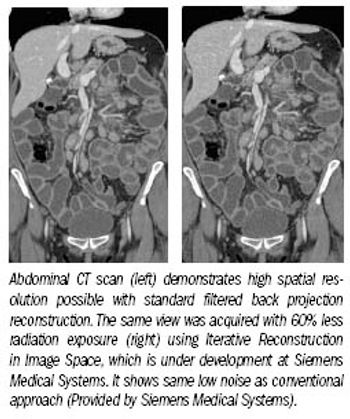

CT vendors have responded to public concerns about radiation dose with innovations that promise to cut patient exposure substantially without affecting imaging service operations.